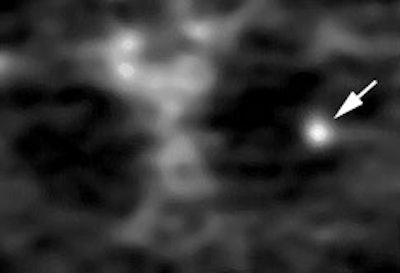

Example: The CT scan in this patient demonstrated a small nodule in the left upper lobe (black arrow). PET-FDG images demonstrate very intense accumulation of the tracer within the lesion (white arrow), which was a non-small cell lung cancer. (Case courtesy of H. Page McAdams MD, Department of Radiology, Duke University Medical Center)